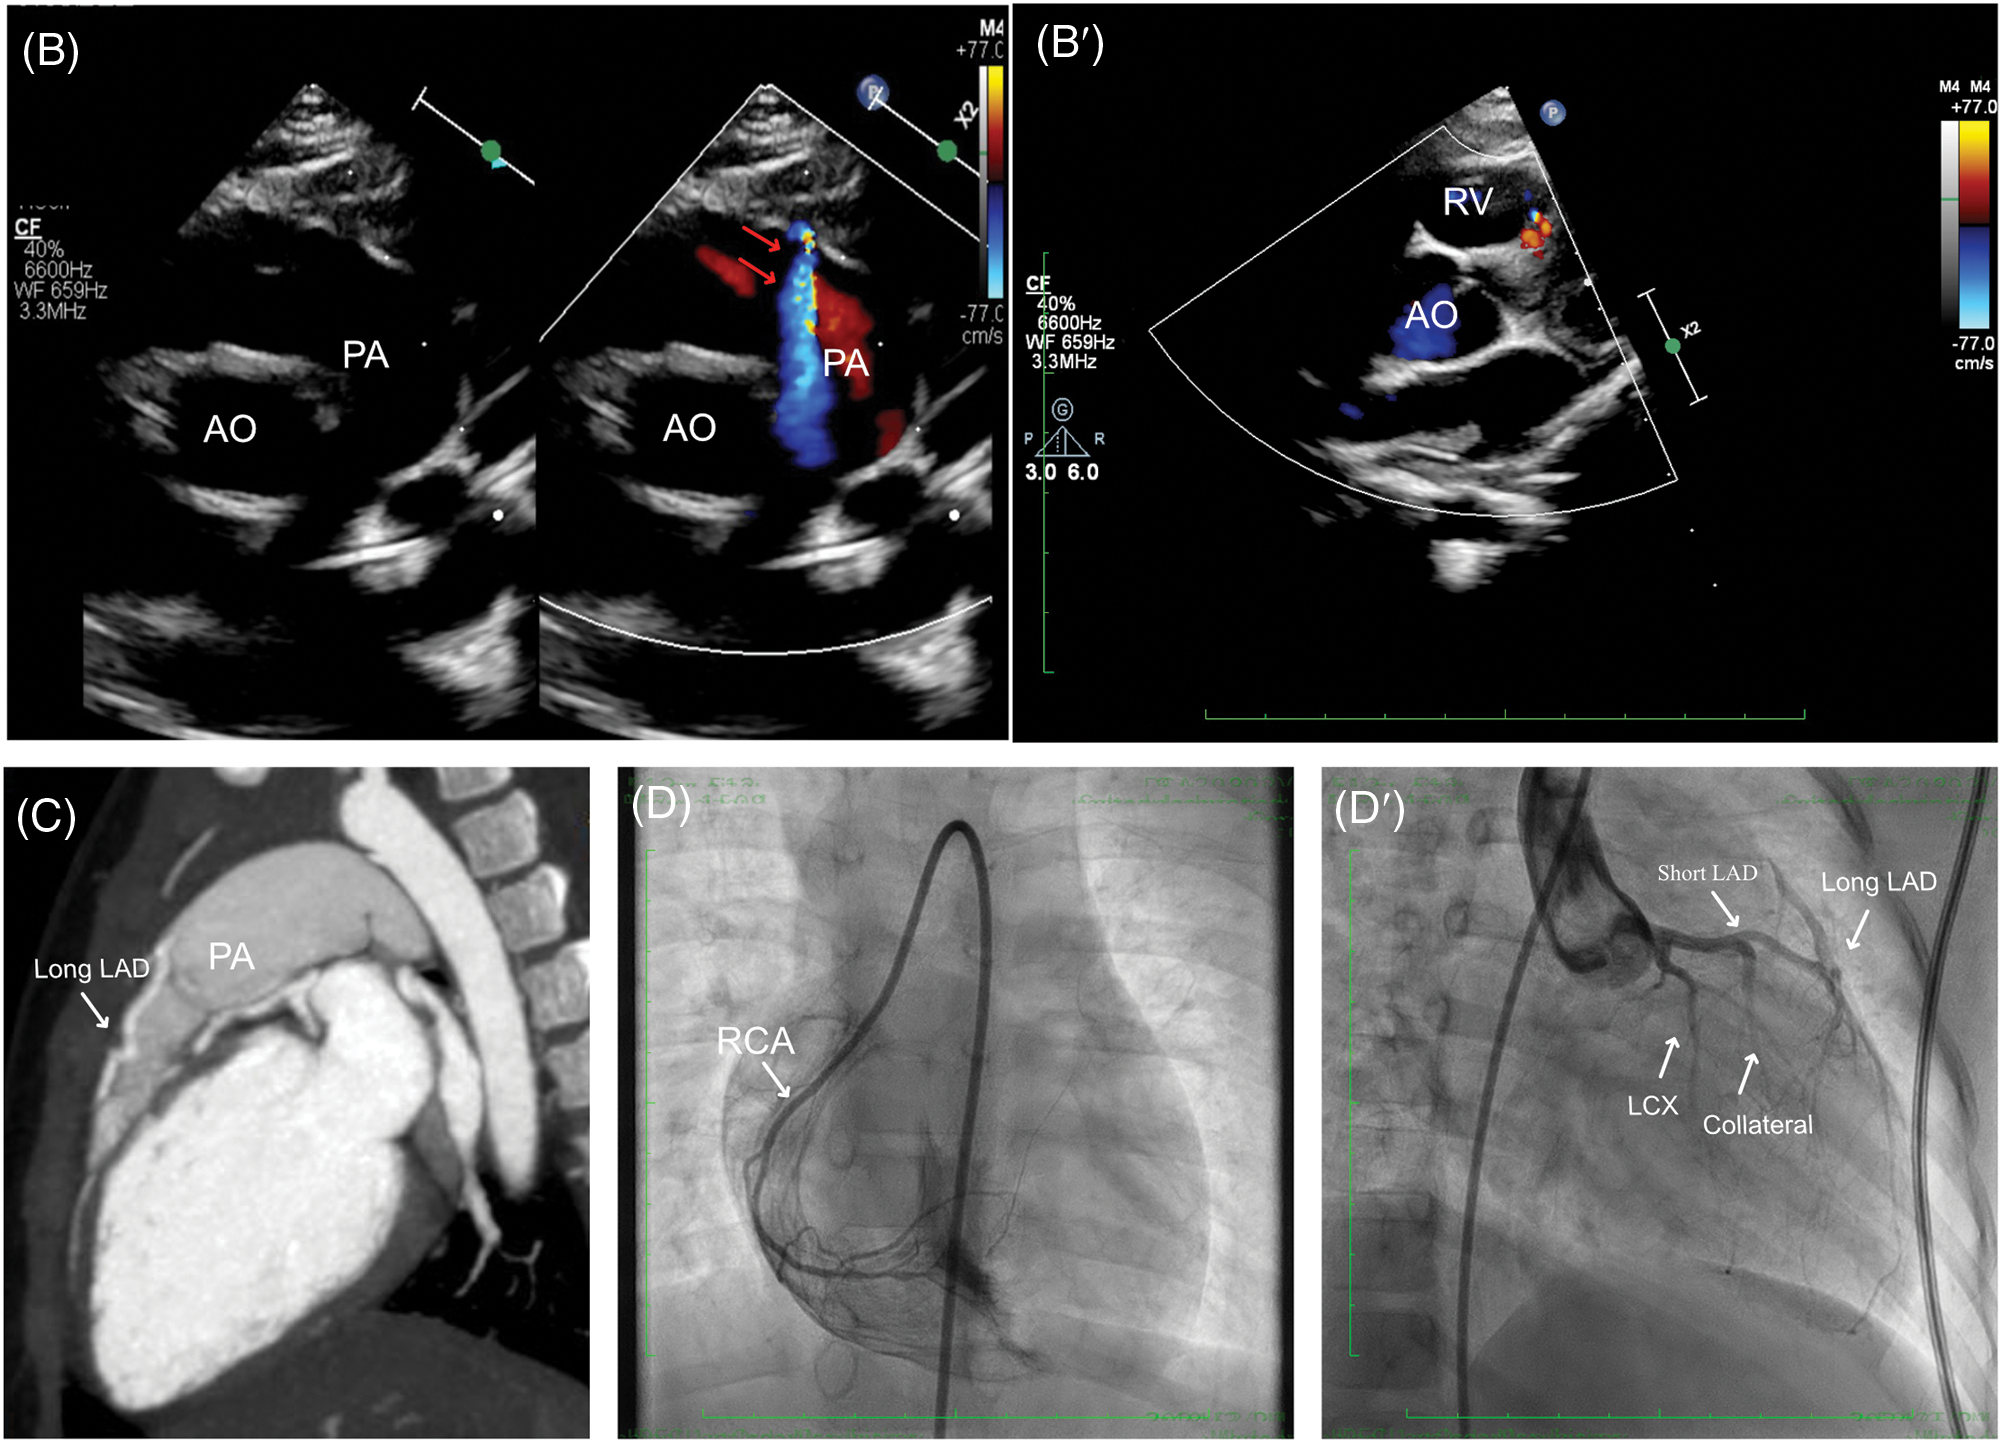

The second case was a 38-month-old female who was admitted to our cardiac department for transcatheter closure for patent ductus arteriosus (PDA). Despite the absence of chest pain symptoms, a routine ECG was performed, demonstrating sinus rhythm without any abnormalities, especially for ST-T segment changes and q waves (Fig. 2A). A detailed echocardiography was conducted, revealing a residual shunt between the aorta and PA was demonstrated, indicating a PDA lesion with a 4 mm diameter. The echocardiography also showed LMCA normally arising from the aortic sinus with a mild dilation of 2.6 mm, LCX, and slender tortuous coursing LAD originated from the LMCA. At the same time, abnormal blood shunting flowed into the right ventricle. Additionally, another abnormal blood shunt draining into PA. These non-invasive assessments suggested differential diagnoses among PDA, small coronary artery-PA fistula, and coronary artery-right ventricle fistula (Fig. 2B,B′). A CTA examination was then conducted to illustrate the three branches of coronary arteries, which revealed dominant functional LCX from LMCA and the RCA’s typical origin in RCS. The LMCA originated from the LCS and emitted a short LAD, while a long margining LAD coursed in the interventricular groove, originating from PA (Fig. 2C). However, the CTA did not reveal multiple collateral branches between the short and long LADs. After that, the transcatheter angiography was performed before PDA closure, which demonstrated a long LAD originating from PA coursing to the apex of the left ventricle in the interventricular groove. The short LAD was given by the LMCA, with several collateral communicating branches connecting the RCA and long LAD. Besides, some small vessels drained blood into the right ventricle at the septal myocardium (Fig. 2D,D′, Video S2).

Figure 2: Clinical manifestation of the Case II. (A) Sinus rhythm without any abnormalities. (B, B′) Echocardiography indicated a malformation of small coronary artery-PA fistula (red arrows), and coronary artery-right ventricle fistula. (C) CTA demonstrated LMCA originated from the LCS and emitted a short LAD, while a long margining LAD coursing in the interventricular groove which originated from PA. (D, D′) Transcatheter angiography revealed a short LAD perfused a set of communicating branches to the septum myocardium and the long LAD which was draining a few volumes of blood into PA. CTA, cardiac computed tomography angiography; ECG, electrocardiogram; LAD, left ascending coronary artery; LMCA, left main coronary artery; PA, pulmonary artery; AO, aorta